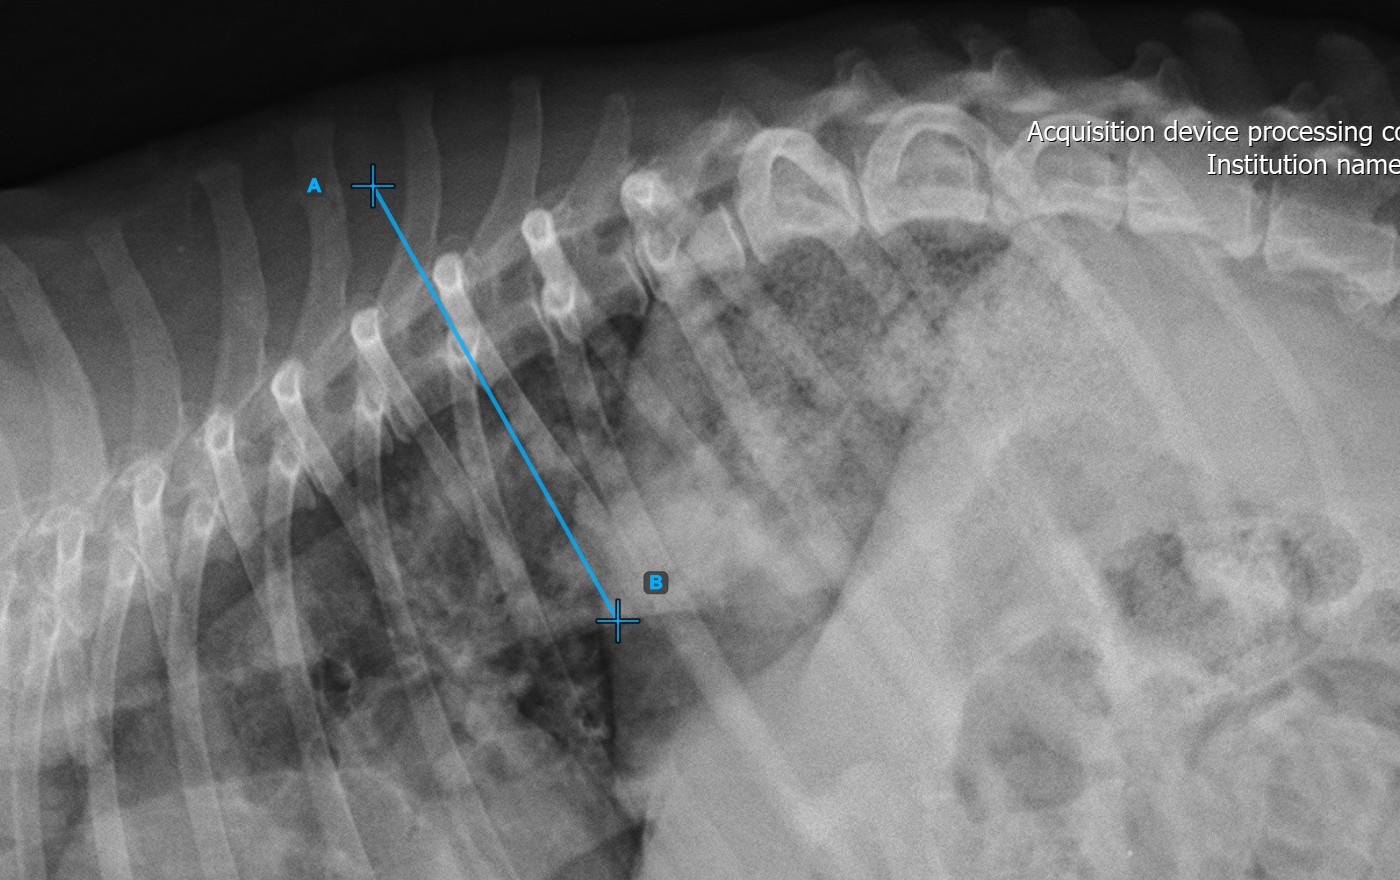

Start the measurement by marking the first vertebral line on the spine.

Identify the vertebral endplate at the initial point of the largest spinal curve deformity. Place the start and end point of the first vertebral line precisely along the identified endplate. Adjust each point on the scene to better align the line with the endplate if needed.

The image below represents a typical placement of the first vertebral line.